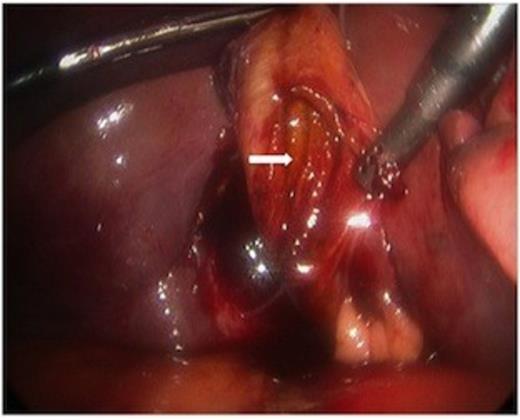

Minimal additional blunt dissection exposed the cystic artery and duct. A critical view of safety was achieved so that cholecystectomy could be performed. Only a small amount of oozing was noted from the liver laceration, following removal of the gallbladder. Haemostasis was achieved with topical agents. The pathologic specimen showed acute inflammation with perforation (Figure 4).